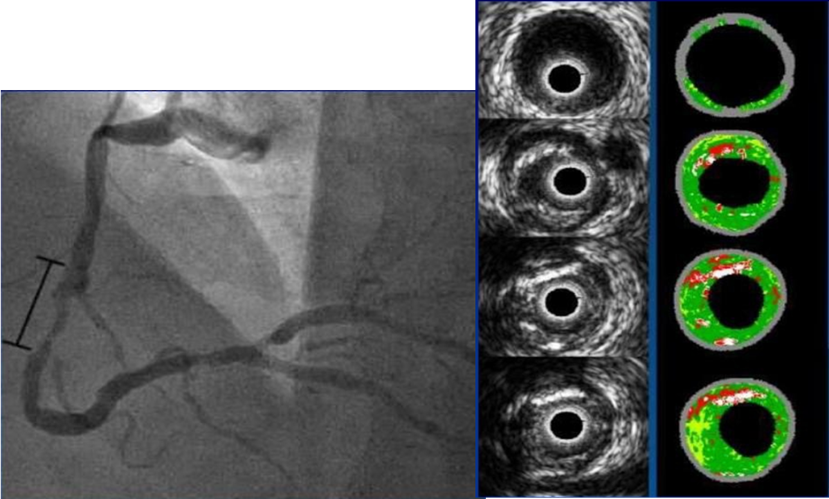

Σύγκριση IVUS και OCT στο ίδιο αγγείο

Οι δύο κύριες τεχνικές ενδοστεφανιαίας απεικόνισης είναι η ενδοαγγειακή υπερηχογραφία (IVUS) και η οπτική συνεκτική τομογραφία (OCT).

Ειδικότερα, η ενδοαγγειακή υπερηχογραφία χρησιμοποιεί υπερηχητικά κύματα που εκπέμπονται από έναν καθετήρα τοποθετημένο εντός του αγγείου. Στόχος της μεθόδου είναι η  δημιουργία εικόνων του αγγειακού τοιχώματος και των αθηρωματικών πλακών.

Από την άλλη, η  οπτική συνεκτική τομογραφία χρησιμοποιεί φως μικρής συνοχής (συνήθως υπέρυθρο φως)  για τη λήψη εικόνων υψηλής ανάλυσης από το εσωτερικό των αγγείων. Αυτή η τεχνική παρέχει λεπτομερή απεικόνιση της δομής της πλάκας και της επιφάνειας του ενδοθηλίου. Έτσι, καθίσταται ιδανική για την αξιολόγηση μικρών βλαβών και τη διάγνωση ενδοστεφανιαίων θρόμβων ή δυσλειτουργιών των stent.